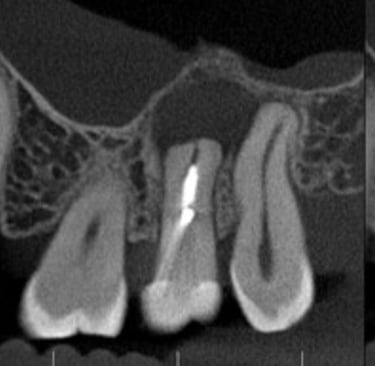

Aspecto Tomográfico Final do Enxerto e Planejamento Digital para o Implante

O enxerto de biomateriais possibilita a colocação de implantes mesmo em pacientes com pouco osso na região posterior da maxila, garantindo suporte seguro e duradouro para reabilitações

A cirurgia guiada utiliza planejamento digital e guias cirúrgicos impressos em 3D, oferecendo maior precisão, menor tempo de cirurgia e recuperação mais confortável.